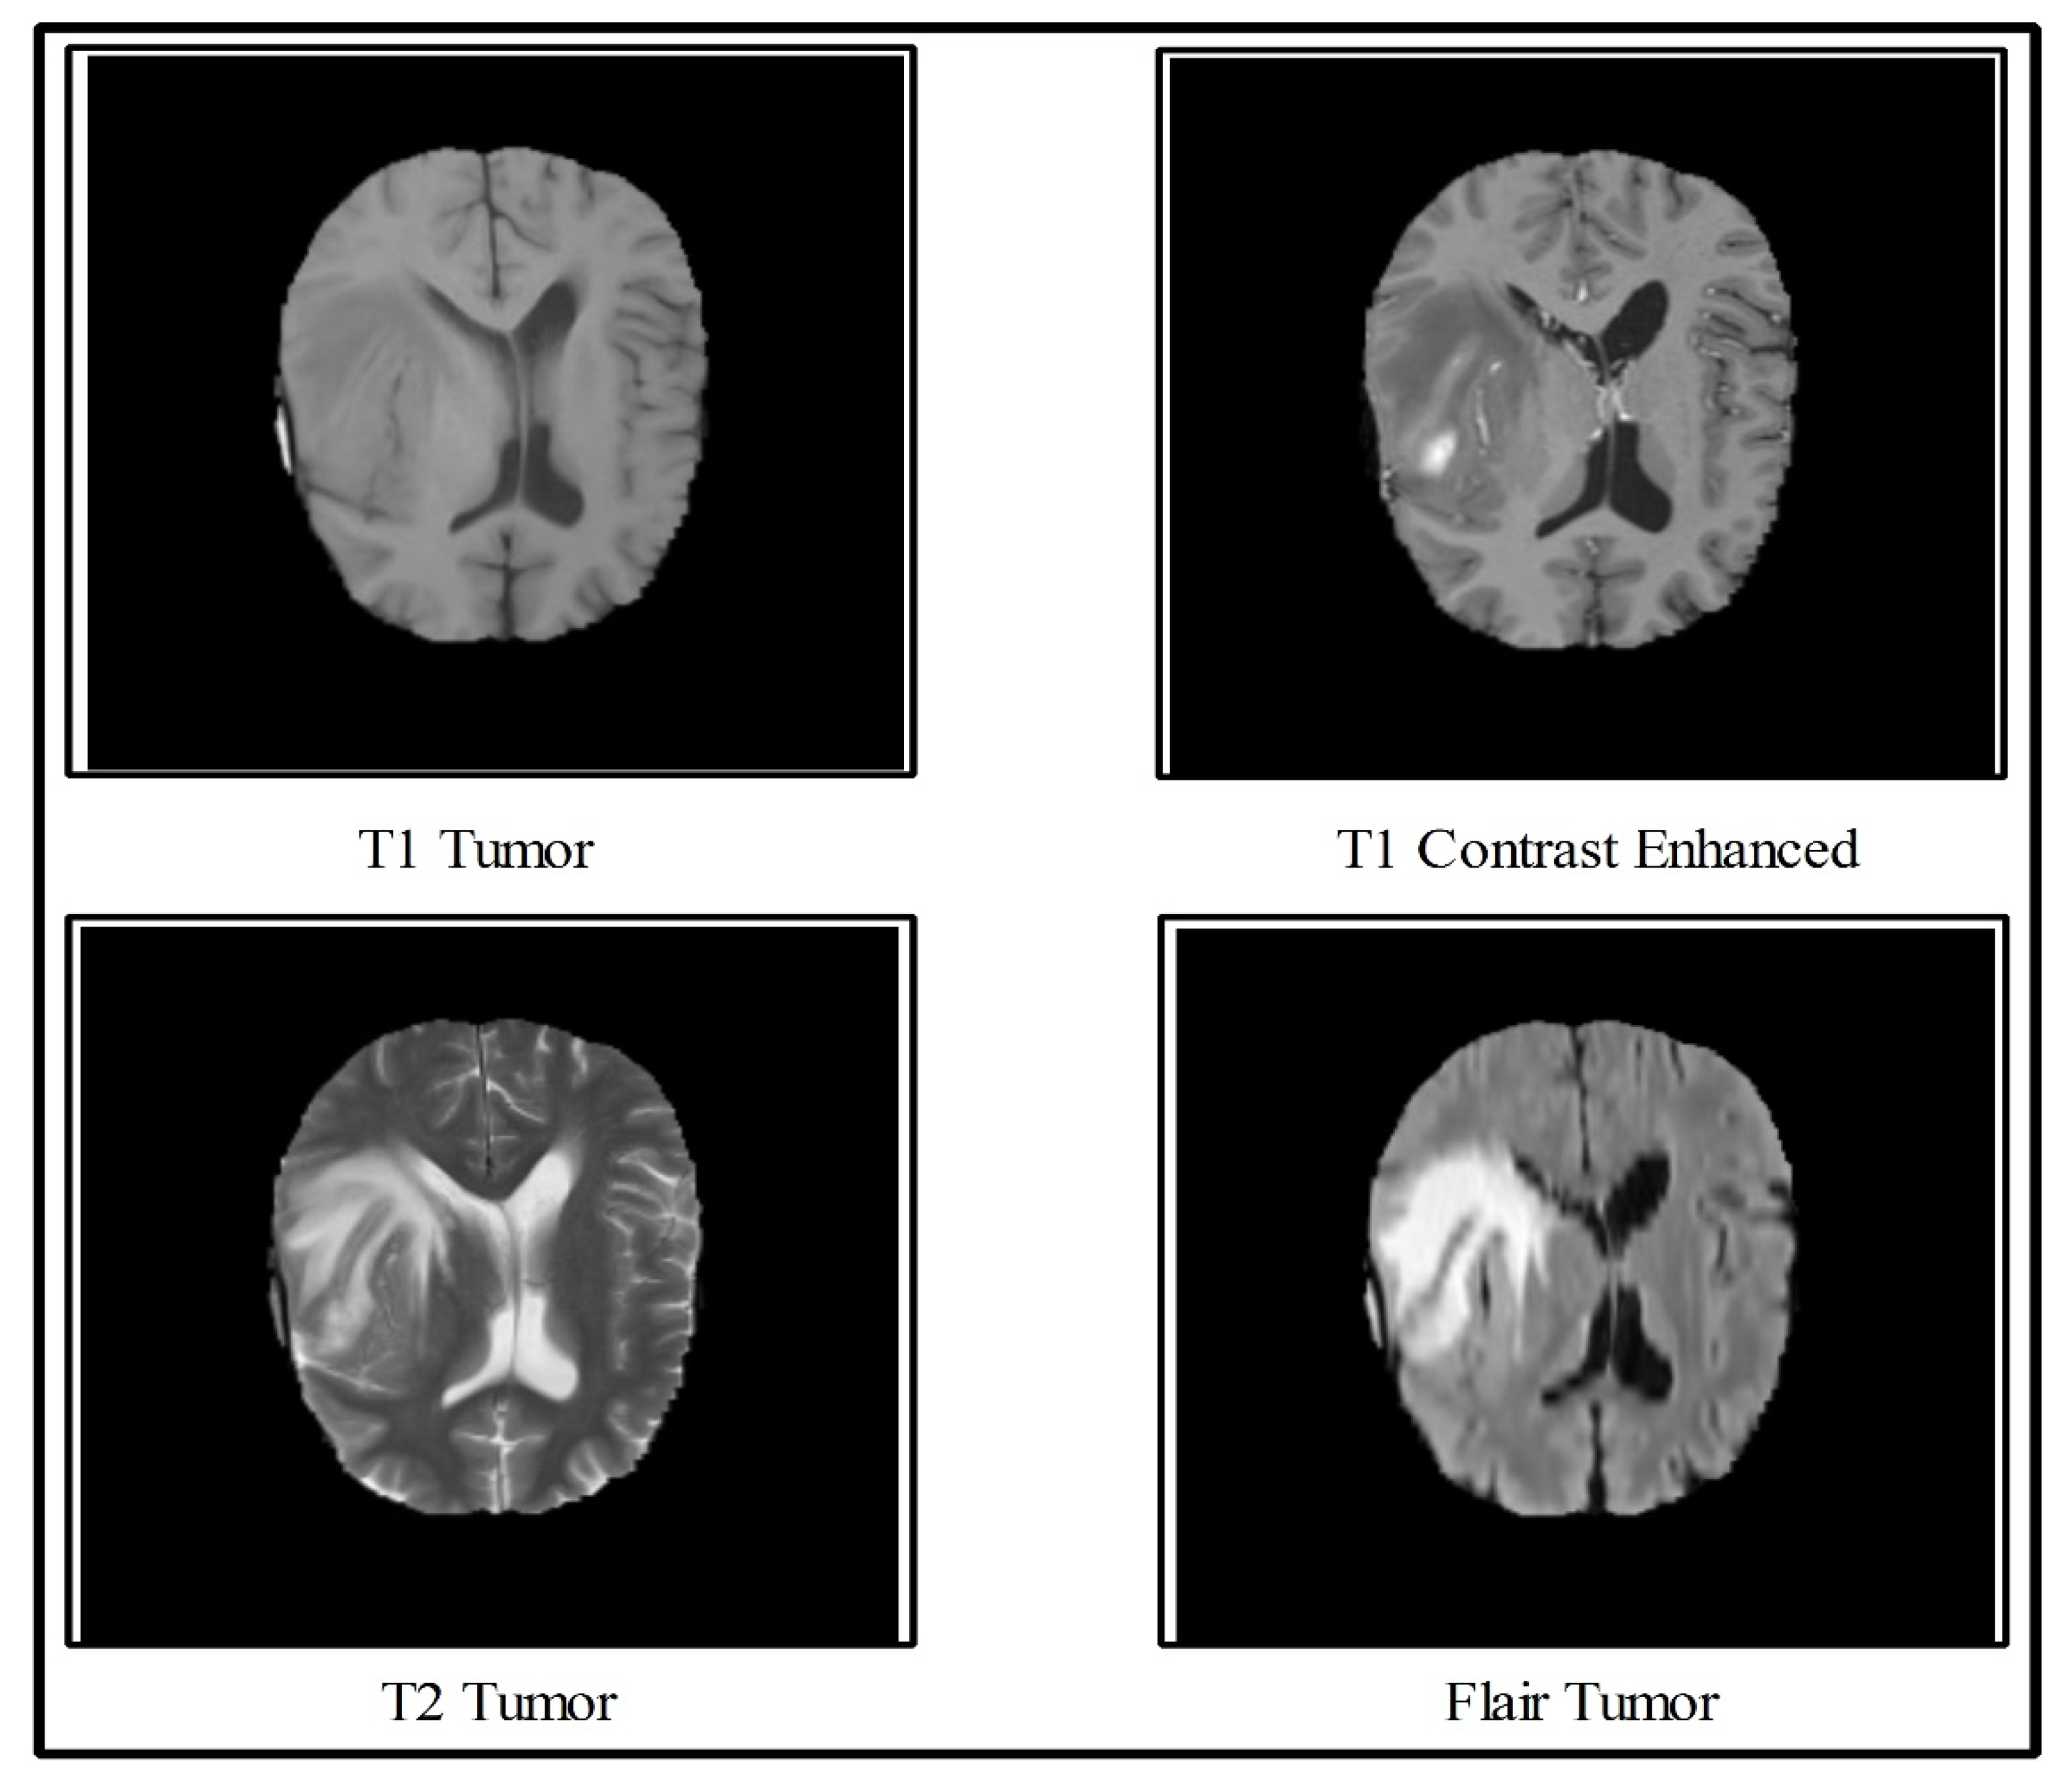

Performed data augmentation on the medical image datasets and finely tuned the hyperparameters of the model.Exploited TensorFlow framework to build a CNN model

X- Ray Image Classification using CNN,